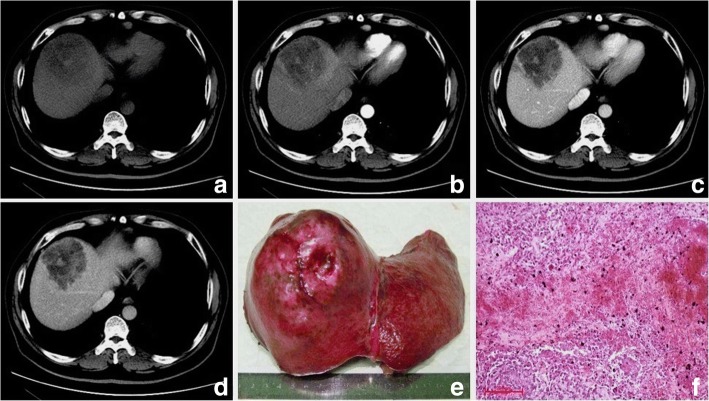

Fig. 2.

Sarcomatous intrahepatic cholangiocarcinoma in a 55 year-old man. Pre-contrast T1WI and T2WI weighted images exhibit a subcapsular mass with multilocular cystic changes and hemorrhage (a, b). The mass is inhomogeneous restricted with an obviously decreased diffusivity in the center ©. The hypo-vascular mass mainly shows irregular peripheral rim enhancement on the arterial phase (d), followed by centrally progressive enhancement with septa on the equilibrium phase (e), and capsule formation is found (f). The tumor is ruptured with hemorrhage found in the subcapsular space (white arrow) (b) and invades the diaphragm (d). The bisected specimen shows a fragile solid and partially necrotic white to tan mass with massive hemorrhage inside and around the tumor (f). H & E stain shows a fibrous capsule, separating the normal liver from tumor cells. The neoplastic cells with pleomorphism have a poor cell adhesion (g)

The imaging features of PHSC are summarized in Table 3. All of the tumors were located near the liver subcapsular area (Figs. 1, 2, 3, 4, 5, 6 and 7), with an obvious dominance (90%) in the right lobe. Tumors ranged in diameter from 3.4 cm to 22.0 cm with a mean diameter of 8.3 cm. The most common gross morphology was massive (six cases) with round or oval shapes, and the remaining included nodular (two cases), infiltrative (one case) (Fig. 5), and multinodular confluent patterns (one case) (Fig. 6). Six tumors were poorly defined, especially at CT (five cases) and the rest were demarcated at MRI. The density or signal of the tumors was mainly heterogeneous (eight cases) for hemorrhage or necrosis. The hemorrhage was found in 1S-HCC and 2 S-ICCs, with one S-ICC rupturing into the subcapsular space as shown on MR imaging (Fig. 2). Five complete or partial capsules (Figs. 2 and 4) were found on CT (one case) or MRI (four cases) and two of them were pathologically confirmed in the S-ICC and S-HCC–CC.

All of the five tumors with MR examinations were mainly hypointense on T1WI and hyperintense relative to liver parenchyma on T2WI and DWI. Bright signal intensity similar to that of cyst or hemangioma on T2WI was seen in 1 S-ICC and 2 S-HCCs. The S-ICC presented multiple cystic changes accompanied by fibrous septum and was inhomogeneous restricted with an obviously decreased diffusivity in the center (Fig. 2). The signal with hyperintensity on T1WI and hypointensity on T2WI indicating hemorrhage was found not only inside the center of the tumor but also the subcapsular space (Fig. 2). The 2 S-HCCs showed homogeneous high signal on DWI and T2WI.

Regarding the distribution of enhancement, peripheral enhancement was seen in 2 S-ICCs and 3 S-HCCs (Fig. 3). Mix rim and internal heterogeneous enhancement (Fig. 4) was found in 2 S-HCCs, internal heterogeneous enhancement was shown in 2S-HCCs and 1 S-HCC–CC (Fig. 6), and no homogeneous pattern was observed. Eight tumors including 2 S-ICCs, 5 S-HCCs and 1 S-HCC–CC were hypo-vascular (Figs. 1, 2, 3 and 4) and the remaining 2 S-HCCs mainly presented hyper-intense enhancement on the arterial phase. As to the enhancement degree of the solid part in the tumor, six tumors showed hyper enhancement compared to the background liver.

With respect to the dynamic pattern of enhancement, of the ten tumors, 40% with 2 S-HCCs and 2 S-ICCs showed peripheral enhancement on the arterial phase and progressive enhancement towards the center (Fig. 2) on the later phases, 20% with 2 S-HCCs showed heterogeneous enhancement on the arterial phase and progressive or persistent enhancement on the later phase (Figs. 2, 3, 4 and 5), and 30% with 3 S-HCCs presented obvious peripheral and heterogeneous enhancement on the arterial phase and then wash out peripherally and partially on the later phase, mimicking ordinary HCC. The remaining S-HCC–CC exhibited a variable enhancement character for its multinodular change (Fig. 6). The tumor showed mild inhomogeneous enhancement on the arterial phase, and the portion near the subcapsular area of the tumor showed persistent thin rim enhancement accompanied by an mural nodular on the portal and equilibrium phase, next to the cyst change was the mild to moderate progressive fill-in enhancement, and the upper portion presented washout on the equilibrium phase.

On the MR imaging of five patients, bright signal intensity similar to that of cyst or hemangioma on T2WI might be explained by necrosis [14] and the signal might be attributed to hemorrhage seen as hypointensity or hyperintensity on T1WI and hypointensity on T2WI not only inside the center of the tumor but also in the subcapsular area. The other S-HCCs showed inhomogeneous high signals on DWI and T2WI, similar to the “normal” type. Five tumor capsules were observed on imaging, and only two of them were confirmed in pathology. It was reported that a high incidence was correlated with well differentiated HCC and the tumor capsules were much more common in ordinary HCC when compared with the S-HCC [5]. Similar to the result, we did not find capsules in S-HCCs, except for a complete capsule in the S-ICC and a partial one in the S-HCC-CC pathologically.

All of the PHSCs in our study located near the liver subcapsular area where the liver capsules were frequently involved (five of seven) and sometimes subcapsular metastasis or peritoneal seeding (three of 10) occurred. The invasion of the liver capsular in sarcomatous carcinoma was more common than that in the “normal” type, which might be explained by the sarcomatoid component [20]. It was found that one of mass-forming S-ICCs with a subcapsular rupture in our study protruded out of the liver contours, involve diaphragm and resulted in multifocal tumor seeding. To the best of our knowledge, four of the 30 S-ICCs reported in the English literature presented with spontaneous rupture thus far [14, 27]. The spontaneous rupture of hepatic tumor was the result of a complex interaction of various factors such as location, composition or pressure and so on [28–30]. The “normal” cholangiocarcinoma seldom ruptured spontaneously as a hard tumor with abundant fibrous stroma. Nevertheless, the S-ICC in our study presented as multiple cysts indicating more necrosis and less fibrous stroma, resulting in a fragile tumor. In comparison to the “normal” cholangiocarcinoma, the S-ICC was prone to rupture.